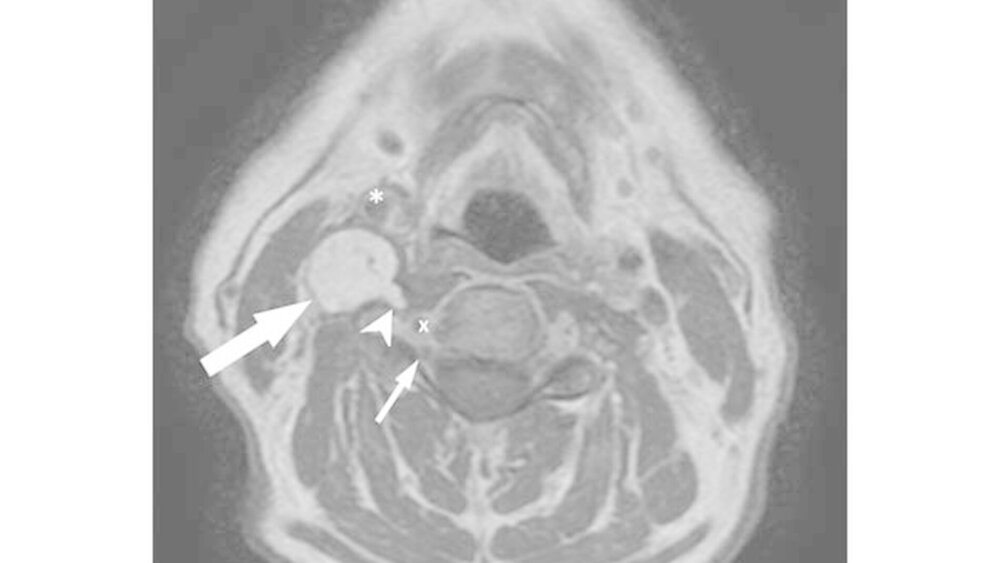

Im MRT zeigte sich korrelierend zum Tastbefund eine spindelförmige Raumforderung mit den Ausmaßen von 5x2x2cm paravertebral auf Höhe HWK 3 bis HWK 6 (Abbildung 1). Der Befund verdrängte sowohl den prävertebrale M. longus colli als auch die Arteria carotis nach ventral.

Die Vena jugularis interna war subtotal komprimiert. Kleinere Ausläufer der Raumforderung lagen unmittelbar lateral des Neuroforamens der Radix C5, unterhalb des HWK 4 und reichten bis auf 3mm an die Arteria vertebralis heran (Abbildung 2). Ein infiltratives Wachstum war radiologisch nicht nachweisbar.